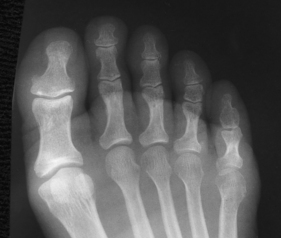

The foot consists of 26 bones (Figs. 6-1 and 6-2):

Each foot has 14 phalanges—2 in the great toe and 3 in each of the other toes. The phalanges of the great toe are termed the distal and proximal phalanges. The phalanges of the other toes are termed the proximal, middle, and distal phalanges. Each phalanx is composed of a body and two expanded articular ends—the proximal base and the distal head.

The five metatarsals are numbered one to five beginning at the medial or great toe side of the foot. The metatarsals consist of a body and two articular ends. The expanded proximal end is called the base, and the small, rounded distal end is termed the head. The five heads form the “ball” of the foot. The first metatarsal is the shortest and thickest. The second metatarsal is the longest. The base of the fifth metatarsal contains a prominent tuberosity, which is a common site of fractures.

Beneath the head of the first metatarsal are two small bones called sesamoid bones. They are detached from the foot and embedded within two tendons. These bones are seen on most adult foot radiographs. They are a common site of fractures and must be shown radiographically (see Fig. 6-2).

The interphalangeal (IP) articulations, between the phalanges, are synovial hinges that allow only flexion and extension. The joints between the distal and middle phalanges are the distal interphalangeal (DIP) joints. Articulations between the middle and proximal phalanges are the proximal interphalangeal (PIP) joints. With only two phalanges in the great toe, the joint is known simply as the IP joint.

The distal heads of the metatarsals articulate with the proximal ends of the phalanges at the metatarsophalangeal (MTP) articulations to form synovial ellipsoidal joints, which have movements of flexion, extension, and slight adduction and abduction. The proximal bases of the metatarsals articulate with one another (intermetatarsal articulations) and with the tarsals (tarsometatarsal [TMT] articulations) to form synovial gliding joints, which permit flexion, extension, adduction, and abduction movements.